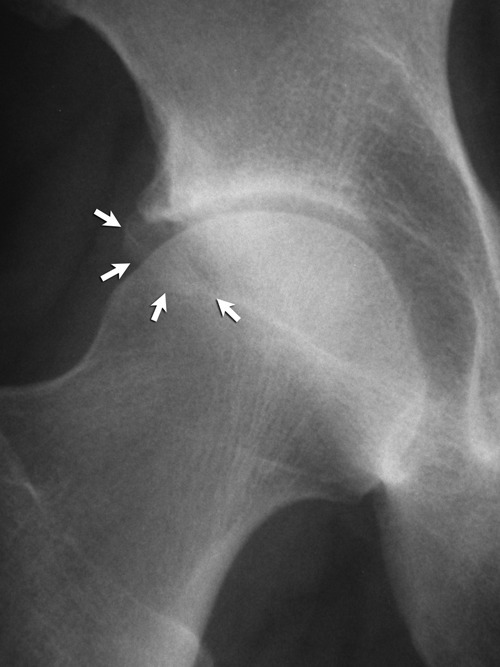

El pinzamiento femoroacetabular** es una entidad patológica que se presenta en las consultas del aparato locomotor y que cursa con dolor e impotencia funcional de la cadera en el adulto joven. Se produce por un conflicto de espacio entre el componente femoral y el anillo acetabular en determinadas posiciones de la cadera.

Femoroacetabular impingement** is a condition where the bones of the hip are abnormally shaped. Because they do not fit together perfectly, the hip bones rub against each other and cause damage to the joint.

En la exploración se aprecia: maniobra de impingement (+), se realiza con el paciente en decúbito supino, llevando la extremidad hacia la flexión de cadera de 90o y en esta posición se realiza, en suave aducción, rotación interna de cadera; si existe algún grado de pinzamiento femoroacetabular se produce dolor, siendo entonces positivo el test.

Femoroacetabular impingement causes pain in the hip in young adults and may predispose to the development of osteoarthritis. Genetic factors are important in the aetiology of osteoarthritis of the hip and may have a role in that of femoroacetabular impingement.